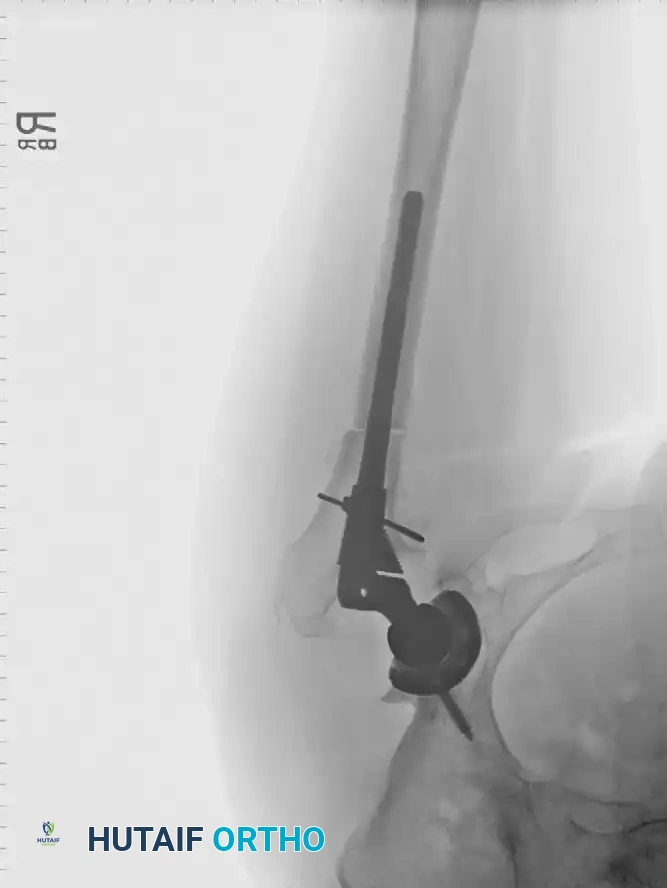

To safely remove prior grafts, the surgeon should utilize a high-speed burr and flexible reamers. Intraoperative fluoroscopy with the broach in place is highly recommended to ensure complete graft removal, proper alignment, and optimal cortical contact.

Radiographic Case Examples: Osteonecrosis and Complex Femoral Reconstructions

Advanced osteonecrosis with subchondral collapse and secondary arthritis.

Intraoperative imaging showing retained fibular graft from a previous joint-preserving procedure.

Use of a high-speed burr to clear the intramedullary canal of sclerotic graft remnants.

Fluoroscopic confirmation of proper broach alignment after graft removal.

Final seating of a cementless femoral stem in optimal neutral alignment.

Postoperative radiograph confirming excellent fit and fill of the femoral component.

Associated Surgical & Radiographic Imaging

Hutaifortho's Orthopaedic Diagram